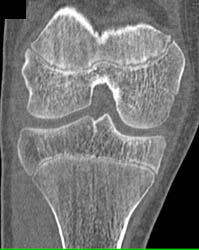

Diagnosis

Pectus Deformity for Pre-op Planning